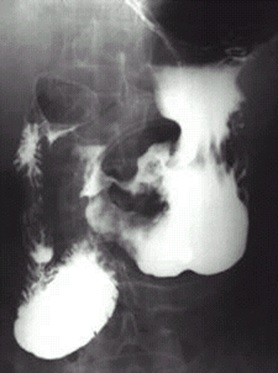

04卷-5.病史:男性,62岁,上腹不适,恶心、呕吐5个月,大便潜血阳性3周。诊断(本题满分2.00分)

C.胃癌

本题答案:C

题目解析:【该题针对“X线-消化道穿孔”知识点进行考核】